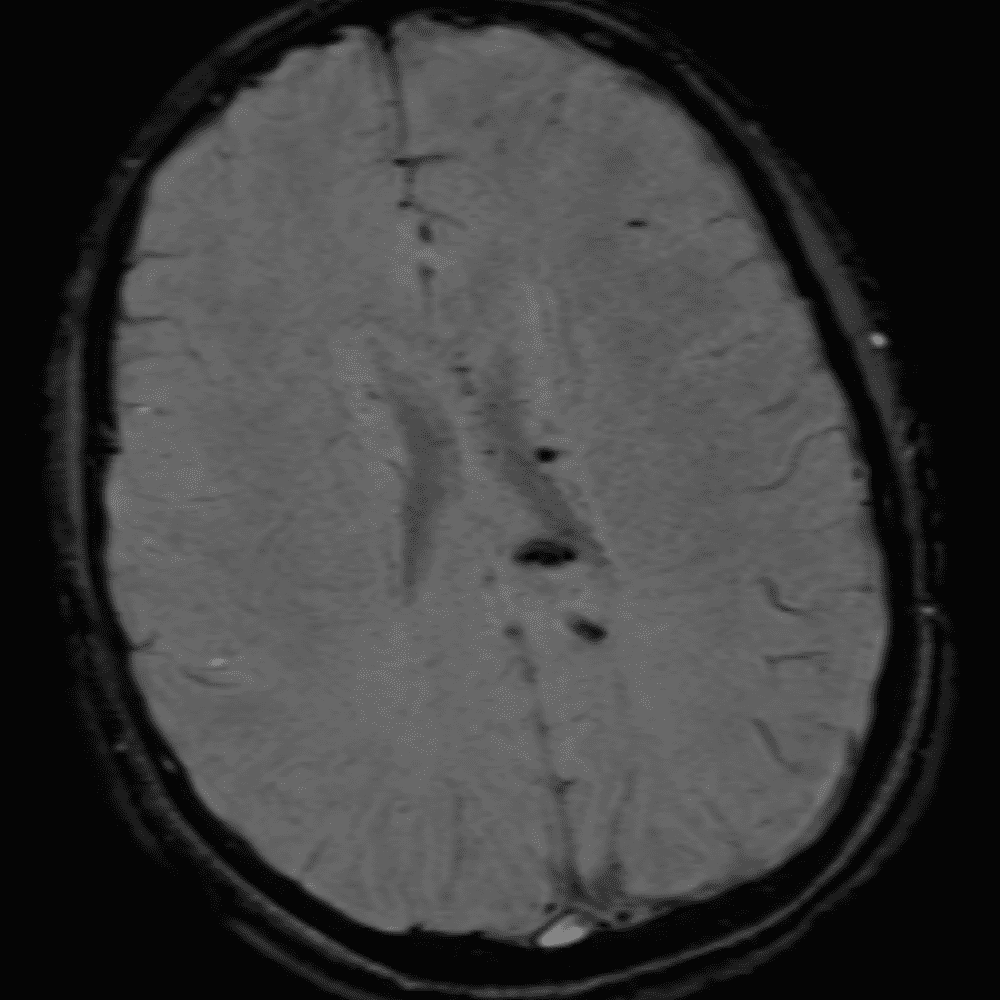

๋‹น์ง ์‹œ ํ”ํžˆ ๋ณผ ์ˆ˜ ์žˆ๋Š” ์‚ฌ๋ก€์˜ ์ „ํ˜•์ ์ธ ์˜ˆ๋ฅผ ํฌํ•จํ•ฉ๋‹ˆ๋‹ค.

39 ์‚ฌ๋ก€

์—ฐ์Šต

๋ฏธ๋ฌ˜ํ•˜๊ฑฐ๋‚˜ ์–ด๋ ค์šด ์‚ฌ๋ก€์™€ ์ผ๋ถ€ ์ •์ƒ ์‚ฌ๋ก€๋ฅผ ํฌํ•จํ•˜์—ฌ ๋‹น์ง์„ ์‹œ๋ฎฌ๋ ˆ์ด์…˜ํ•ฉ๋‹ˆ๋‹ค.

50 ์‚ฌ๋ก€